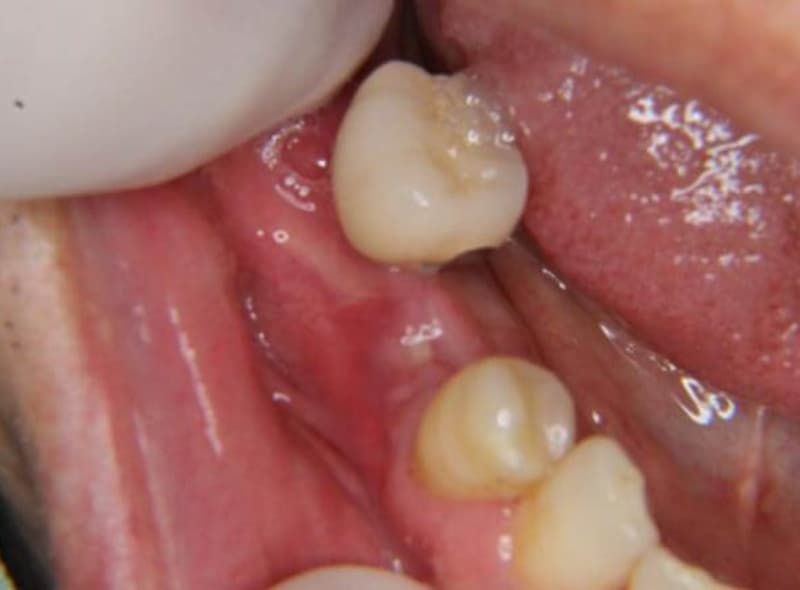

Step03重度歯周病

歯槽骨が溶かされ続け、歯がぐらぐらしてきます。そのため食事がしづらくなったり膿が出てきたりします。歯周炎が重度まで進行してしまうと治癒が非常に困難で、最終的には歯が抜けてしまいます。

歯周病が重度にまで進んでしまうと、スケーリングやルートプレーニングで改善をはかることが難しくなります。

フラップ手術について

フラップ手術は、歯ぐきを切開して歯周ポケットの奥深くにたまった歯石や炎症部分を目で確認しながら除去する方法です。徹底的に清掃するため治療後は、歯周ポケットが浅くなる効果が期待できます。定期的な歯科検診やプロフェッショナルクリーニングと組み合わせると、歯周病の再発を抑えられる可能性が高まります。